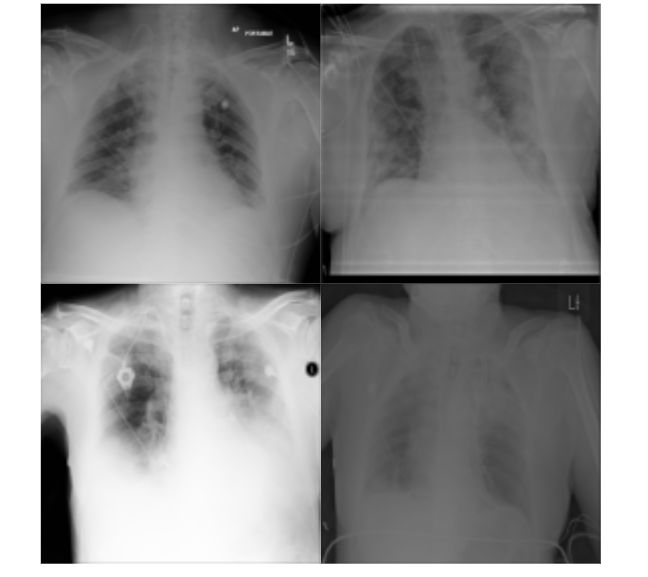

For the training of the proposed approach, we have investigated both positive and control group samples of the QaTa-COV19 dataset. By considering their overall qualities, we have manually annotated a set of samples and grouped them in two categories: poor quality samples {𝐲i}i=1Npsuperscriptsubscriptsubscript𝐲𝑖𝑖1subscript𝑁𝑝\{\mathbf{y}_{i}\}_{i=1}^{N_{p}} and high quality samples {𝐱j}j=1Nhsuperscriptsubscriptsubscript𝐱𝑗𝑗1subscript𝑁\{\mathbf{x}_{j}\}_{j=1}^{N_{h}}. Accordingly, we have labeled Np=2460subscript𝑁𝑝2460N_{p}=2460 poor quality and Nh=2094subscript𝑁2094N_{h}=2094 high quality samples. Samples from the dataset are provided in Fig. 5. Basically, assigning the training samples defines the transformation domains that is going to be learned by the R2C-GAN; therefore, it has a significant effect on the restoration performance. To avoid ambiguity in image domains, we have mainly excluded the mid-quality images in the formation of the training set. In the test phase, the restoration and classification performance evaluations have been performed by randomly selecting 19,2471924719,247 images from the QaTa-COV19 dataset. Overall, Table I presents the number of samples in the selected subset. As the test samples are randomly selected, the image quality varies in the test set, so it may contain poor, medium, and high quality images.

Refer to caption

(a)

(b)

Figure 5: Poor quality (a) and high quality (b) image samples from the QaTa-COV19 dataset.